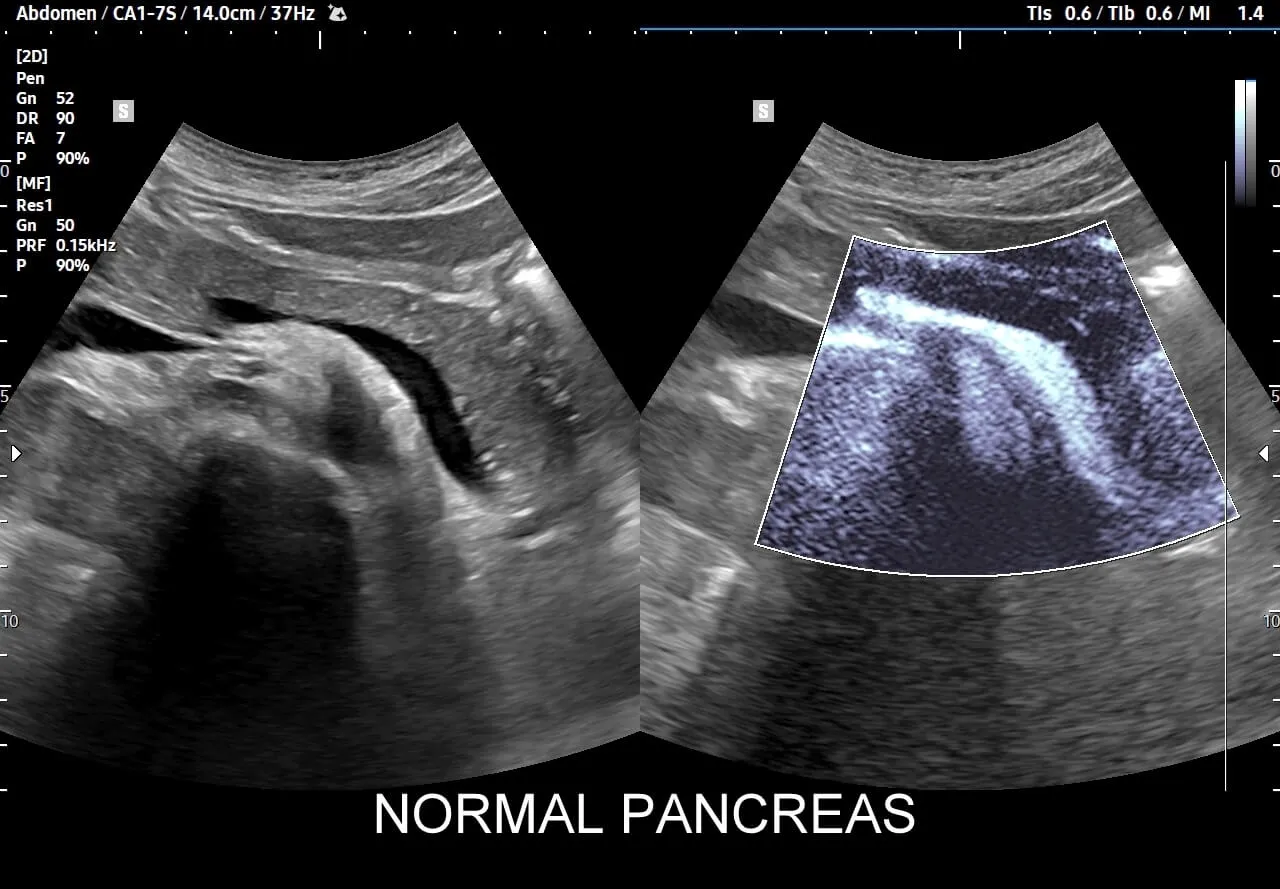

USG jamy brzusznej: pierwsze, bezbolesne spojrzenie na trzustkę

USG jamy brzusznej to podstawowe, nieinwazyjne i łatwo dostępne badanie, które często jest pierwszym krokiem w diagnostyce trzustki. Pozwala mi ocenić wielkość, kształt i ogólną strukturę trzustki, a także wykryć obecność ewentualnych guzów, torbieli czy zwapnień, które mogą świadczyć o przewlekłym procesie zapalnym. Należy jednak pamiętać o jego ograniczeniach na przykład w ocenie ostrego zapalenia trzustki USG może być mniej precyzyjne ze względu na obecność gazów jelitowych. Do badania należy się odpowiednio przygotować: być na czczo, stosować dietę lekkostrawną dzień wcześniej i unikać napojów gazowanych, aby zminimalizować ilość gazów w jelitach.Tomografia komputerowa (TK) kiedy potrzebna jest większa precyzja?